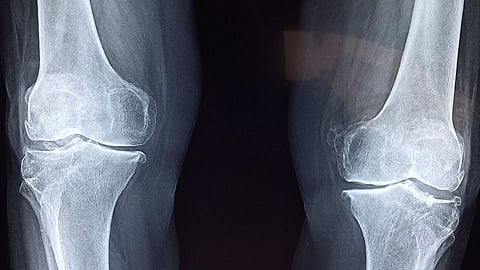

The long bones have cartilages at the end that act as a cushion. The cartilage between the bones helps them glide against each other smoothly. The condition causes the stripping of this layer of cartilage. And the loss of cartilage leads to the loss of joint space and increased density of bone along the joint line.

The constant rubbing of bony surfaces against each other leads to formation of bony spurs that are evident on x-rays. This results in joint pain and stiffness. The most commonly affected areas are the knees, hips, cervical spine, fingers, and wrist joints.